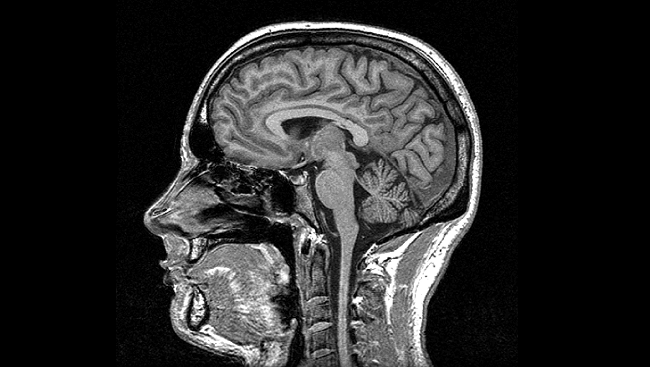

Human Brain MRI Scan Stock Photo. Image Of Accident, Cancer - 37215148

www.dreamstime.com

www.dreamstime.com

mri brain scan human stock vertical section royalty mr